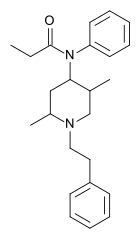

- Part II

The modifications covered in this diagram have to do with carbon skeleton modifications of the original fentanyl molecular structure. These are organized into methyl acetate additions, which are most known for the fentanyl -> carfentanil conversion. Many analogues of great potency, such as ohmfentanyl and lofentanyl posses methyl acetate groups added to the 4-carbon (of the piperidine ring, in the para- position relative to the annular nitrogen). The methyl acetate is added here from the α-carbon of the acetate moiety as it is with ohm- and lofentanyl. The 4-carbon is not a chiral center in carfetnanil because of a lack of piperidinyl subsitutuents, but this same carbon is a chiral center in both ohm- and lofentanyl because both of those analogues have piperidinyl substituents.

The second group are organized into methyl additions, which are known for the fentanyl analogues such as α-methylfentanyl and cis-3-methylfentanyl. These analogues can posses a wide variety of modified pharmacological properties, including increased and decreased potency (receptor binding efficiency), increased or decreased half-life (metabolic binding efficiency) or other side effects on human physiology. Other substituents such as hydroxy, chloro, fluoro, and a wide variety of alkyl groups, are also substituted in place of these methylations to produce psychoactive analogues of fentanyl, but because they often use the same skeletal naming conventions as the simple methyl analogues, we did not reproduce them all in the image here.